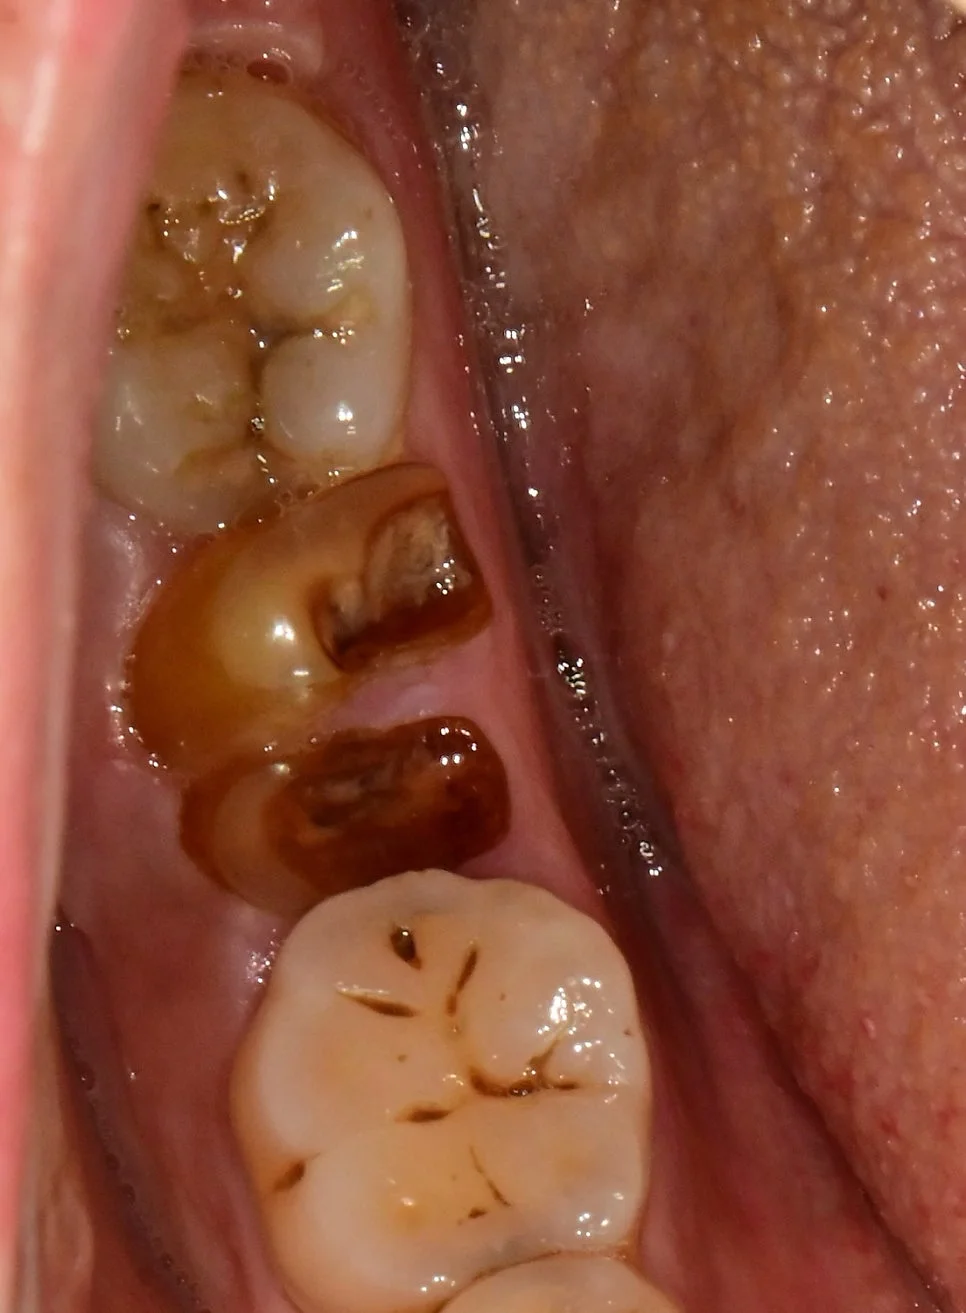

임플란트 실패와 통증의 90% 원인은 바로 ‘감염’입니다. 식립할 자리에 눈에 보이지 않는 세균이 남아 있으면, 뼈와 임플란트가 붙는 것(골유착, Osseointegration)을 방해하고 지속적인 통증을 유발합니다.

저희는 이를 원천 봉쇄하기 위해 강력한 살균 소독제인 클로르헥시딘(Chlorhexidine)과 항생제를 수술 부위에 사용하여 철저히 소독합니다.